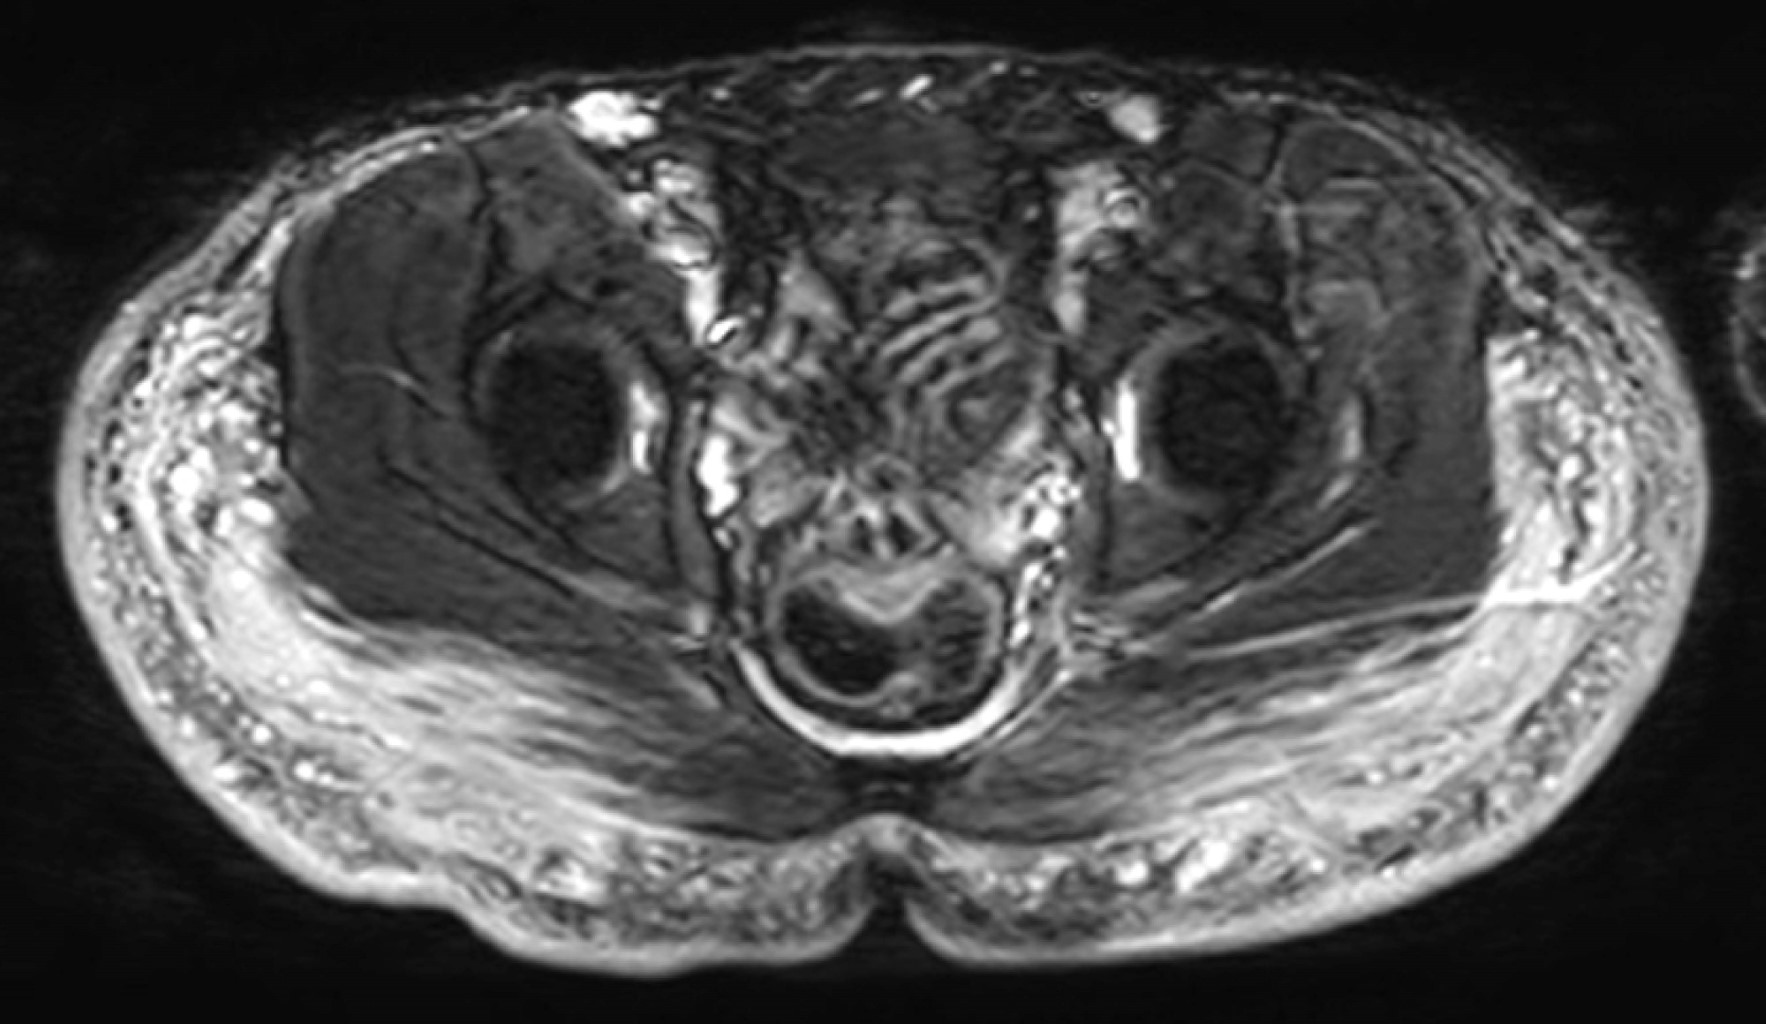

Paciente de 30 años con antecedentes de aplicación de modelantes en las regiones glúteas hace 10 años. Desde hace tres años presenta dolor en ambas piernas, con zonas induradas y cambios de coloración. Se le realizó resonancia magnética de las regiones glúteas y piernas identificando imágenes globulares y lineales irregulares de comportamiento isointenso en el T1, hiperintenso en el T2, hiperintenso en las secuencias de saturación grasa (Fat-Sat) y en STIR (Short Inversion Time Inversion Recovery) con compromiso de los tejidos blandos superficiales y de los planos musculares que afectan a los glúteos mayor y medio (Figuras 1 y 2).

La resonancia magnética es el método de diagnóstico de elección, permite la localización del material modelante, su distribución, extensión y profundidad a los tejidos adyacentes. La mayoría de estas sustancias están compuestas por agua, con comportamiento hipointenso en T1, hiperintenso en T2 y T2 con supresión grasa (STIR, Fat-Sat, SPAIR) y por su alto peso molecular, son hiperintensos en secuencias T2 con supresión de grasa y agua (silicon-only o FSE T2 IR), el tejido inflamado realza con el contraste (gadolinio). Estas características permite identificarlas, pero no ayuda a determinar el material utilizado.3 Los patrones de distribución son: globulares, lineales o pseudonodulares. Pueden existir adenomegalias. Las aplicaciones más frecuentes se dan en las regiones glúteas con repercusión hacia los músculos glúteo mayor y medio.1